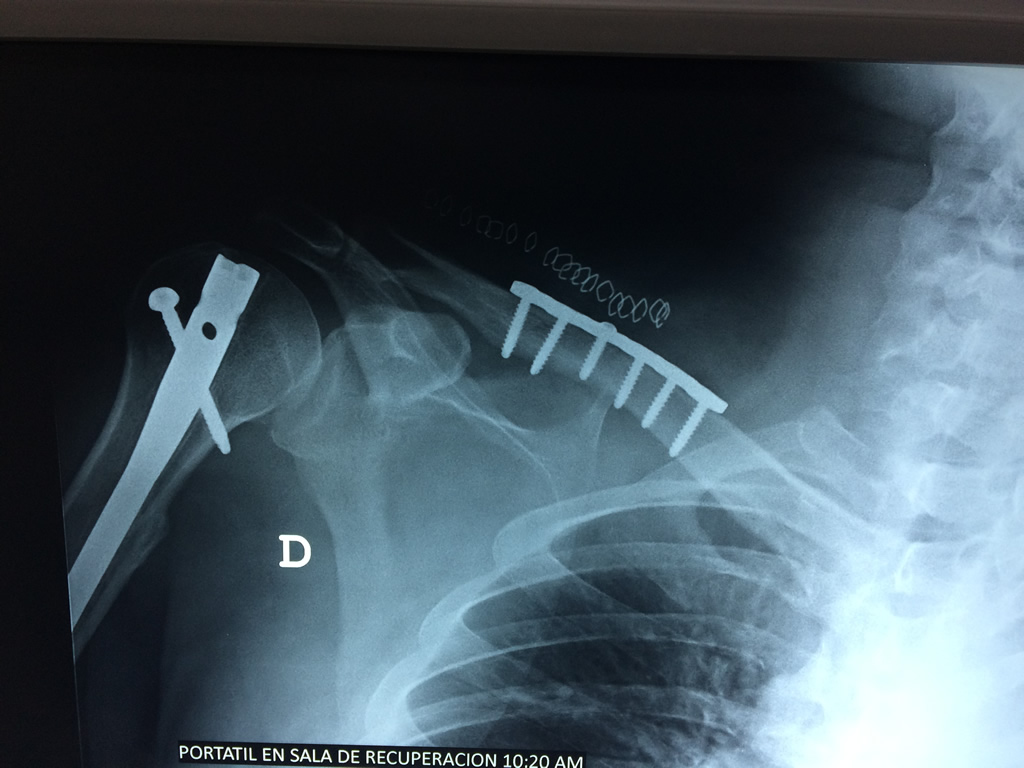

Calcaneo - Clavícula

La clavícula es un hueso largo, con forma de "S" itálica, situado en la parte anterosuperior del tórax. Junto con la escápula forman la cintura escapular. Se puede palpar por toda su longitud y se extiende del esternón al acromion de la escápula, siguiendo una dirección oblicua lateral y posterior.

Se considera el único medio de unión entre el miembro superior y el tórax. A pesar de su aspecto, similar al de un hueso largo, posee una estructura semejante a la de un hueso plano, ya que carece de epífisis y de diáfisis, lo que la harían entrar dentro de la clasificación de hueso largo. Carece de un canal medular propiamente dicho.